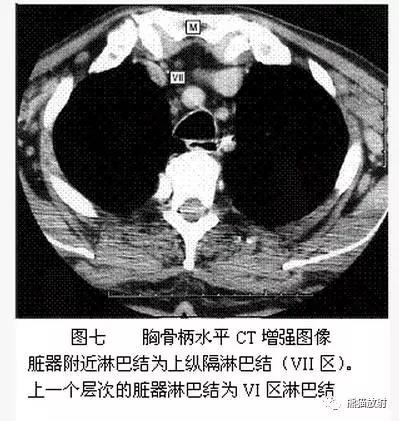

VII区:上纵隔淋巴结

来源:熊猫放射